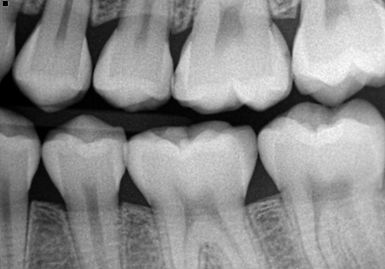

These are the most common type of dental X-rays for children. They show the upper and lower back teeth and are used to detect cavities between teeth. Bitewing X-rays are quick and comfortable, even for young children.